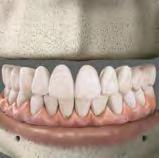

mínimamente invasivo, lo que para el odontólogo restaurador implica proporcionarle tratamientos digitales orto-restaurativos facialmente guiados. Y es que poder realizar el diseño de la sonrisa, el diseño de la prótesis, la planificación ortodóntica y el análisis de la masa dental que se conserva gracias a la integración del movimiento dental en la planificación protésica , ya es posible gracias a herramientas como el sistema Invisalign Smile ArchitectTM , software de Align TechnologyTM que engloba todo el proceso en una única plataforma.

INVISALIGN SMILE ARCHITECT™, EL SOFTWARE DEL FUTURO

Align Technology presentó recientemente Invisalign Smile ArchitectTM , una revolucionaria herramienta, que permite y facilita muchos procedimientos invasivos del pasado en tratamientos mínimamente invasivos centrados en el paciente. Con él, los profesionales pueden diseñar un plan de tratamiento orto-restaurativo digital fácilmente guiado, adaptado a las necesidades de sus pacientes, desde la primera consulta. En definitiva, un software de planificación diseñado para ayudar al clínico a obtener unos resultados más predecibles en la planificación de sus casos. Y es que Invisalign Smile ArchitectTM integra en una sola plataforma el diseño de la sonrisa, el diseño de la prótesis, la planificación ortodóntica y el análisis de la masa dental que se conserva gracias a la integración del movimiento dental en la planificación protésica.

Como afirma la Dra. Lorena Mingotti, «con Invisalign Smile ArchitectTM tenemos la predictibilidad del tratamiento restaurativo. También a nivel comunicativo con nuestros pacientes es una herramienta espectacular, porque les enseñamos, mediante fotos, cómo se va a ver al iniciar el tratamiento y al término del mismo con las restauraciones gracias el diseño que hemos planificado».